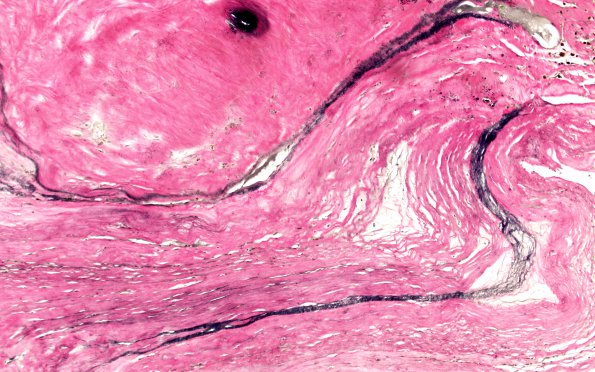

4C5 Giant Aneurysm (Case 4) N18 VVG 20X 2

A convoluted remnant of the internal elastic lamina of this anterior cerebral and pericallosal artery (VVG)